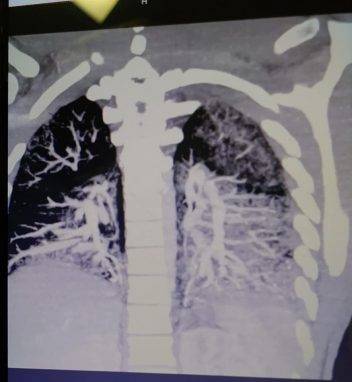

После того, как Энтони был сделан снимок, оказалось, что пресловутые масла в буквальном смысле запеклись в его легких, из-за чего те стали напоминать легкие 60-летнего мужчины, выкуривающего в день по две пачки обычных сигарет.

А ведь коварный недуг подкрался к парню постепенно, сначала его мучил сильный кашель, который врачи попытались вылечить с помощью антибиотиков. Но через несколько дней заядлому вейпоману стало намного хуже, а уровень кислорода в его легких опустился до 36%. И это при том, что показатель ниже 90% уже считается крайне опасным для здоровья человека… Сейчас врачи пытаются «растопить» затвердевшие масла, чтобы вывести их из легких Энтони. При этом медики предупредили парня, что его здоровью был нанесен ущерб, который будет очень тяжело минимизировать.

Вот так выглядят легкие после курения электронных сигарет Фото: фейсбук*/Michael Gallagher